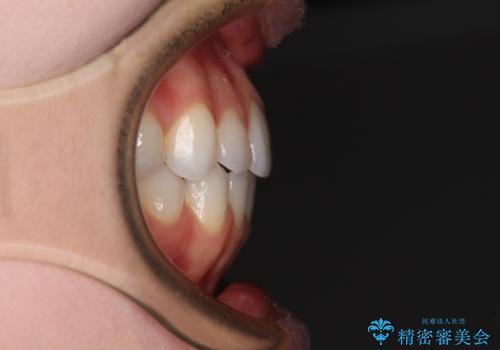

上下前歯が接触しない オープンバイトをインビザラインで改善

上下の奥歯を圧下させるようにすることで、前歯を接触させるように計画しました。